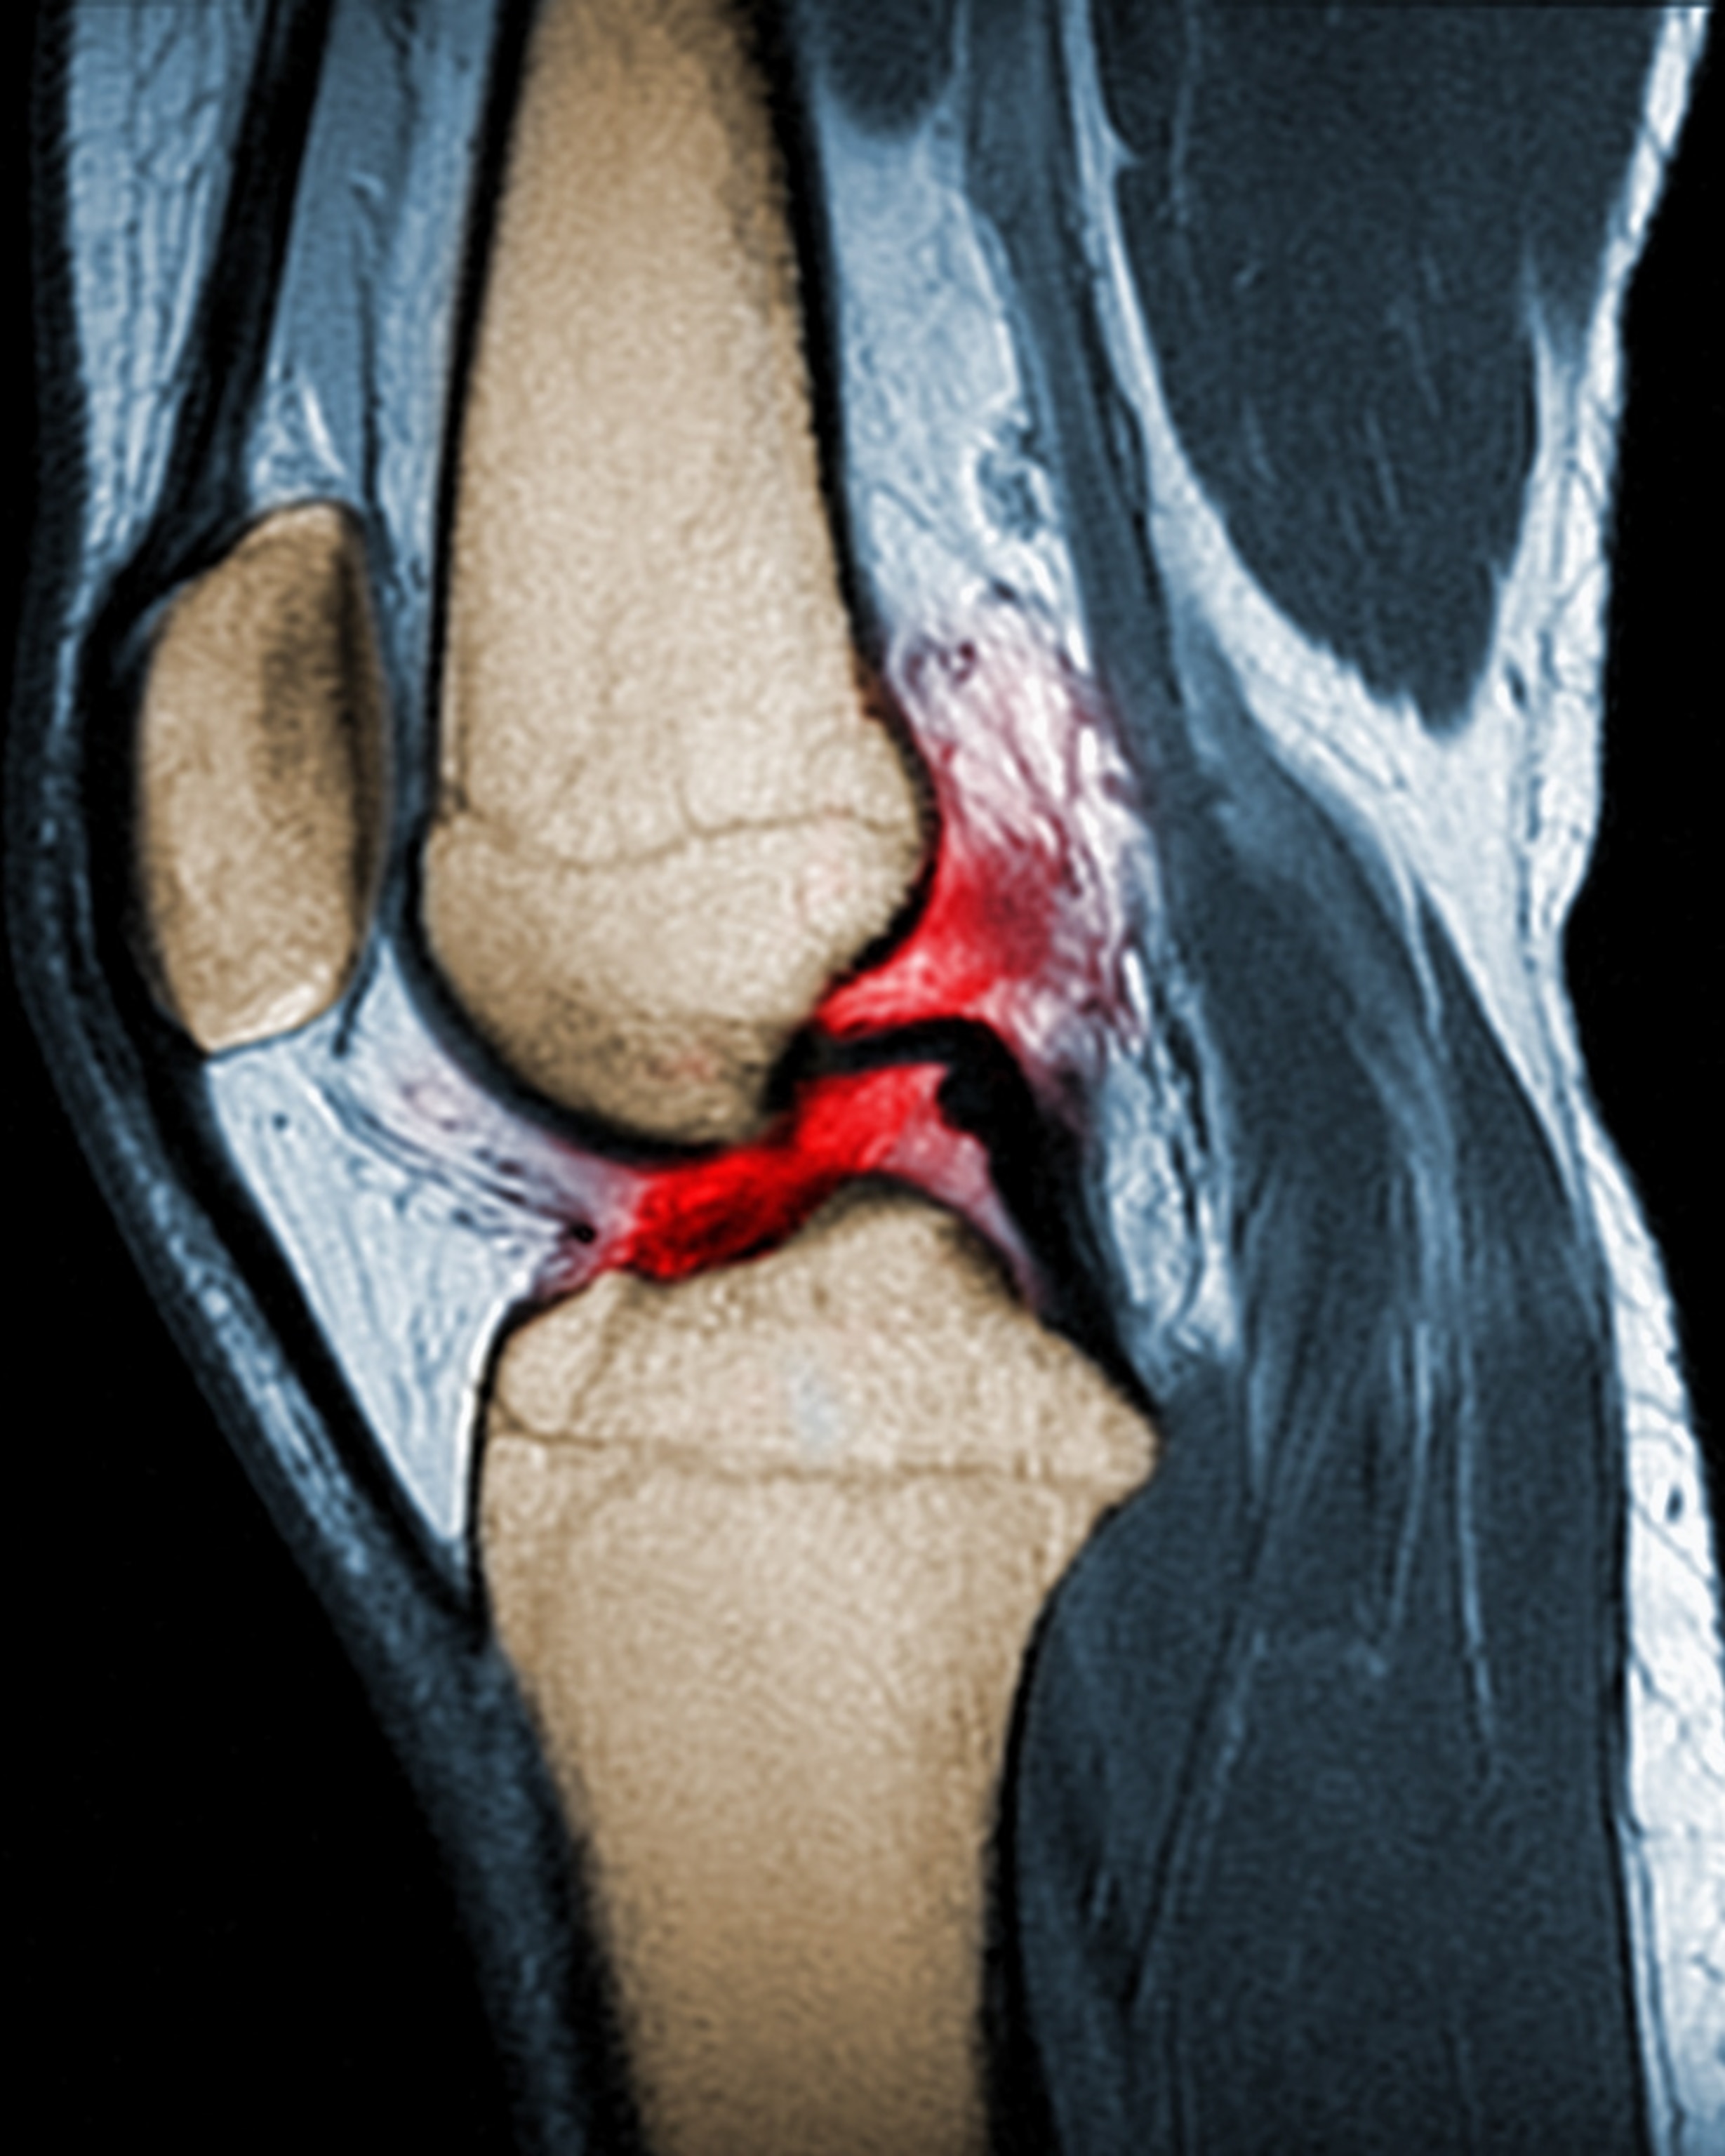

It's high time that ACL tears in girls are women are taken more seriously. An ACL tear can wreak havoc on girl’s and women’s bodies and minds and can be potentially career-ending for elite athletes. When the ACL is completely ruptured, the “gold standard” is surgery, according to Dr. Sara Edwards, an orthopedic surgeon at UCSF’s Women’s Sports Center, usually followed by nine to twelve months of extensive physical therapy. Females are at a higher risk of re-injury and it “can become a lifelong issue,” Edwards says. Kitley remembers, “it's such a long process. . . For me, I missed my last NCAA tournament, and I missed my ACC tournament and then had to be on crutches at the WNBA draft and then couldn't walk for a while. It completely consumes your life and still dealing with new stuff almost two years later is really frustrating.”